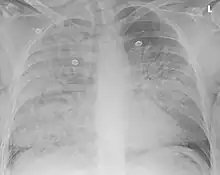

| Aspiration pneumonia in a ventilated person with a central line and nasogastric tube | |

Aspiration pneumonia is typically diagnosed by a combination of clinical circumstances (people with risk factors for aspiration) and radiologic findings (an infiltrate in the proper location).[2] A chest x-ray is typically performed in cases where any pneumonia is suspected, including aspiration pneumonia.[17] Findings on chest x-ray supportive of aspiration pneumonia include localized consolidation depending on the patient's position when the aspiration occurred.[18] For example, people that are supine when they aspirate often develop consolidation in the right lower lobe of the lung.[18] Sputum cultures are not used for diagnosing aspiration pneumonia because of the high risk of contamination.[19] Clinical symptoms may also increase suspicion of aspiration pneumonia, including new difficulty breathing and fever after an aspiration event.[6] Likewise, physical exam findings such as altered breath sounds heard in the affected lung fields may also be suggestive of aspiration pneumonia.[6] Some cases of aspiration pneumonia are caused by aspiration of food particles or other particulate substances like pill fragments; these can be diagnosed by pathologists on lung biopsy specimens.[20]